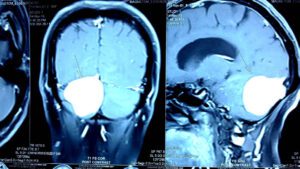

மூளையில் கட்டி: தலைவலிகளிலேயே மிகவும் அபாயகரமானது மூளையில் கட்டிகளால் வரக்கூடிய தலைவலியே ஆகும். ஏனென்றால் ஆரம்ப காலக் கட்டத்தில் மற்ற சாதாரண தலைவலி மாத்திரைகளுக்கே கட்டுப்படும். அதனால் மருத்துவப் பயனாளிகள் அலட்சியமாக இருப்பதற்கு வாய்ப்பு அதிகம். இவ்வகையான தலைவலிகளுக்கு சில அறிகுறிகள் உள்ளன.

நெற்றிப்பொட்டில் வலி: காலையில் எழுந்தவுடன் நெற்றிப் பொட்டில் அதிக வலி இருக்கும். வாந்தி வரும். வாந்தி எடுத்தவுடன் தலைவலி குறையும். தலைவலி மிகவும் அதிகமாகும் தருணத்தில் கண் பார்வை மங்குவதற்கான வாய்ப்புண்டு. இம்மாதிரியான மருத்துவப் பயனாளிகளுக்கு கூடுதலாக கீழ்க்கண்ட சில அறிகுறிகள் இருக்கலாம்.

1. வலிப்பு நோய். 2.கண்பார்வை மங்குதல். 3.காது சரியாக கேட்காமல் இருப்பது. 4. நடந்தால் தடுமாற்றம் ஏற்படுவது. 5. கை, கால்களில் பலம் குறைவாக இருப்பது. சொரணை குறைவாக இருப்பது போன்ற அறிகுறிகள் இருக்கலாம்.

இந்த மருத்துவப் பயனாளிகளை அவசரமாக சி.டி. ஸ்கேன் எடுத்து வைத்தியம் செய்ய வேண்டும்.